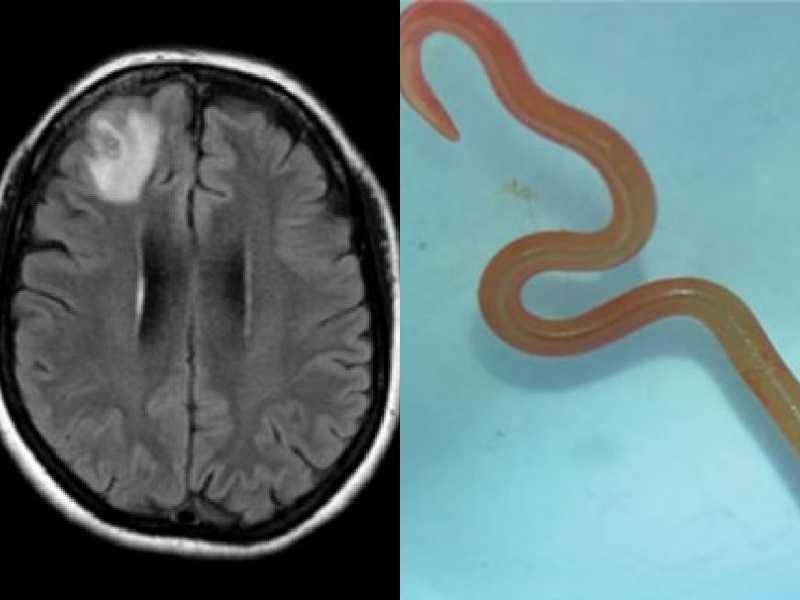

Soffriva di vuoti di memoria e depressione: aveva un verme di 8 centimetri nel cervello

SIDNEY. Accusava da settimane febbre, sudorazione notturna, dolori addominali, dimenticanza e depressione, poi la scoperta: aveva un nematode parassita lungo 8 centimetri, un verme solitamente presente nei pitoni, che si dimenava vivo nel cervello. Il parassita è stato estratto da una donna di 64 anni, in Aaustralia. È il primo caso al mondo di ritrovamento di tale parassita negli esseri umani. La donna, regolarmente monitorata, ora si sta riprendendo bene.